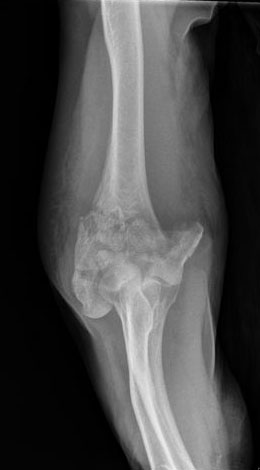

ACT artrosis muy severa de codo.

Fractura de olécranon con osteosíntesis.

ACT Prótesis completa de codo.

Fractura supracondílea de codo.

Fractura supracondílea de codo.Tras reducción y osteosíntesis.

Fractura supracondílea de codo. Tratamiento con agujas.